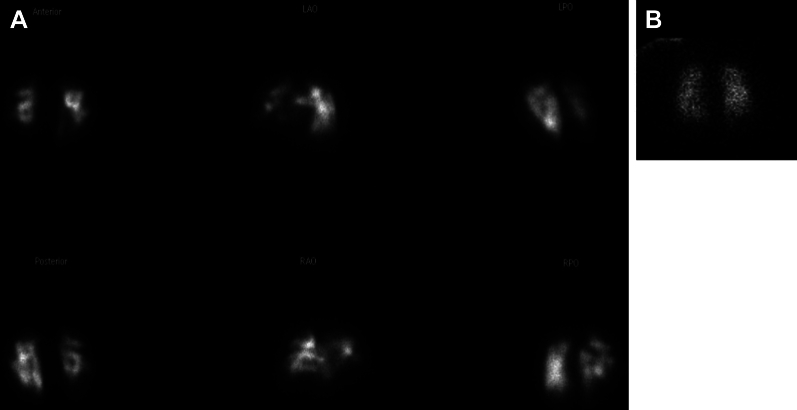

Balloon pulmonary angioplasty (BPA) is an evolving treatment modality for patients with chronic thromboembolic pulmonary hypertension (CTEPH) who are not candidates for pulmonary endarterectomy. Although several imaging modalities currently exist for evaluating CTEPH, their individual use, specifically in the clinical practice of BPA, has not been well described. In this article, we provide a preprocedural, intraprocedural, and postprocedural interventional imaging roadmap for safe and effective BPA performance in routine clinical practice. Preprocedural assessment includes transthoracic echocardiography for right ventricular assessment, ventilation/perfusion scan to identify pulmonary segments with the highest degree of hypoperfusion, cross-sectional chest imaging excluding alternative causes of mismatched defects and providing anatomic and perfusion imaging concurrently, and nonselective invasive pulmonary angiography for risk stratification of individual lesion subtypes. Intraprocedural assessment includes subselective segmental angiography (SSA) for delineating segmental and subsegmental branch anatomy, lesion identification, and vessel sizing. Intravascular ultrasound and optical coherence tomography serve as adjunctive intraprocedural tools for more accurate vessel sizing and lesion characterization when SSA alone is insufficient. Postprocedural considerations include chest radiography to monitor for immediate postprocedure complications and echocardiography for the interval assessment of the right ventricle on longer-term follow-up.

对于不适合进行肺动脉内膜切除术的慢性血栓栓塞性肺动脉高压(CTEPH)患者来说,球囊肺血管成形术(BPA)是一种不断发展的治疗方式。虽然目前有多种成像模式可用于评估 CTEPH,但它们各自的用途,特别是在 BPA 临床实践中的用途,还没有得到很好的描述。在本文中,我们为常规临床实践中安全有效地实施 BPA 提供了一个术前、术中和术后介入成像路线图。术前评估包括用于评估右心室的经胸超声心动图、通气/灌注扫描以确定灌注不足程度最高的肺段、横断面胸部成像以排除造成不匹配缺损的其他原因并同时提供解剖和灌注成像,以及用于对个别病变亚型进行风险分层的非选择性有创肺动脉造影。术中评估包括亚选择性节段血管造影术(SSA),用于划分节段和亚节段分支解剖结构、病变识别和血管大小。血管内超声和光学相干断层扫描可作为术中的辅助工具,在单靠亚选择节段血管造影不足以确定血管大小和病变特征时,可用于更准确地确定血管大小和病变特征。术后注意事项包括胸片检查,以监测术后即刻出现的并发症,以及超声心动图检查,以便在长期随访中对右心室进行间隔评估。